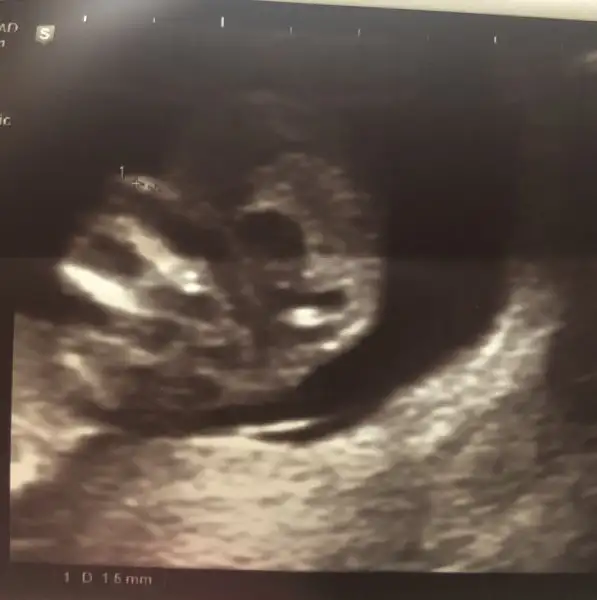

İkincisi burun kemiği ölçümü